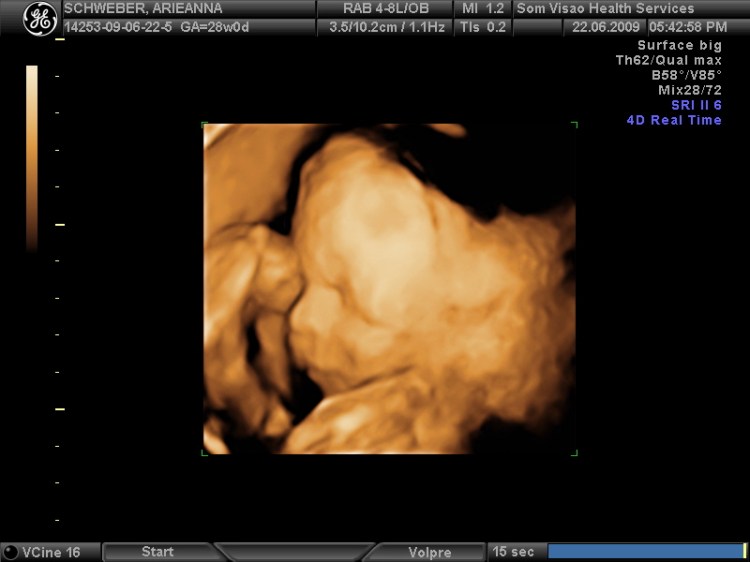

3D Ultrasound - Ianiv & Arieanna - Flickr¿Qué es un ultrasonido 3D?

Al igual que sus contrapartes bidimensionales, los ultrasonidos 3D usan ondas de sonido de alta frecuencia y un software de imagen especial para crear imágenes de los tejidos blandos, los órganos y otra anatomía de su bebé. Pero los ultrasonidos 3D producen imágenes mucho más nítidas y claras de su pequeño. “La tecnología 3D ha mejorado enormemente la calidad de las imágenes de ultrasonido”. “Proporcionan imágenes muy realistas, de calidad fotográfica”.

Una ecografía 3D se realiza como cualquier otra ecografía. Primero, el médico o técnico frotará gel en su vientre y luego moverá un transductor por el área. El transductor dirige las ondas sonoras hacial útero y el bebé que está dentro, brindándole una imagen de su bebé en desarrollo.